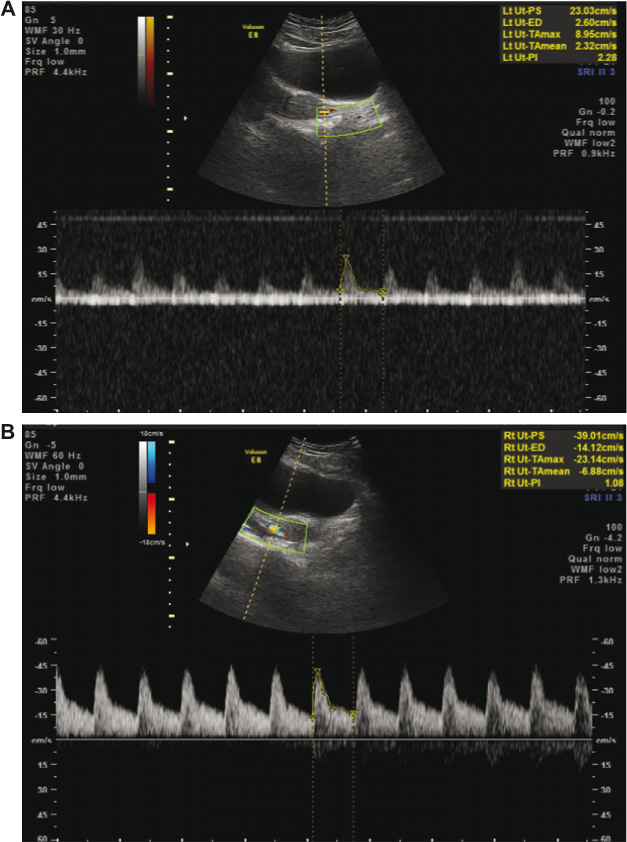

On 2-D and 3-D transvaginal US 3 weeks after UAE, the right ovary, contralateral to UAE, showed a volume of 8.2 cm3, while the left ovary showed a volume of 4.2 cm3. Three-dimensional US demonstrated an arcuate uterus in the coronal plane (Figure 1) with hyperechogenic bands within the endometrium, suggestive of intrauterine adhesions. Pulsed Doppler waveform signals from the untreated right uterine artery showed a pulsatility index (PI) of 1.08 and a resistive index (RI) of 0.63 (Figure 2A). The pulsed Doppler waveform signals from the treated left uterine artery showed a PI of 2.28 and RI of 0.78 (Figure 2B).

Pulsed Doppler waveform signals obtained from the left uterine artery demonstrated a PI of 2.28 (A). Pulsed Doppler waveform signals obtained from the right uterine artery demonstrated a PI of 1.08 (B).

The ensuing follow-up by color Doppler and 3-D power Doppler US can assess revascularization following UAE. Previous studies have recorded Doppler sonography of the uterine arteries post embolization showing normal revascularized uterine arteries [1]; however, these patients were already pregnant, rendering the predictive value of these studies meaningless. On the basis of the color and pulsed Doppler assessment at the 3 weeks follow-up, the left, embolized uterine artery showed decreased flow with increased PI and RI compared with the untreated right uterine artery. It is expected that formation and propagation of collaterals will further improve uterine blood flow, leading to restoration of fertility. UAE is a viable intervention for PPH in women who desire to preserve future fertility, while pulsed and 3-D power Doppler is a non-invasive tool for detecting causes of obstetric complications, evaluating structural and circulatory changes before and after UAE, and evaluating patients’ future fertility prospects [4].